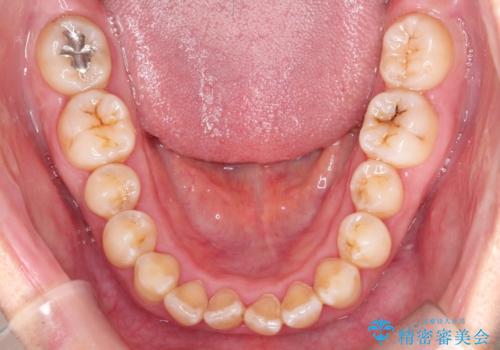

【インビザライン】前歯のすきまを閉じたい

- 前歯の隙間を主訴に来院されました。

インビザライン にて治療を行い、歯並びを改善することができました。